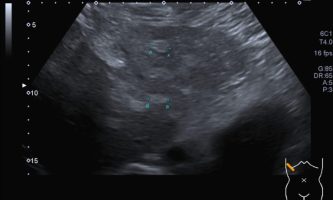

El médico de referencia le indica nueva ecografía de control, donde se observan múltiples y extensas lesiones focales hepáticas hiperecogénicas, redondeadas y confluentes, las cuales predominan en adyacencia a venas supra hepáticas, sin condicionar efecto de masa y sin alteración de la superficie hepática(fig. 1 y 2). Ante la valoración con Doppler color no presenta patrón de flujo peri ni intralesional y respeta el calibre de las venas supra hepáticas(fig. 3 y 4). Dada las características ecográficas se sospecha esteatosis focal multinodular confluente como principal diagnóstico presuntivo, siendo los diagnósticos diferenciales patologías de naturaleza infecciosa, tumoral o metastásica.